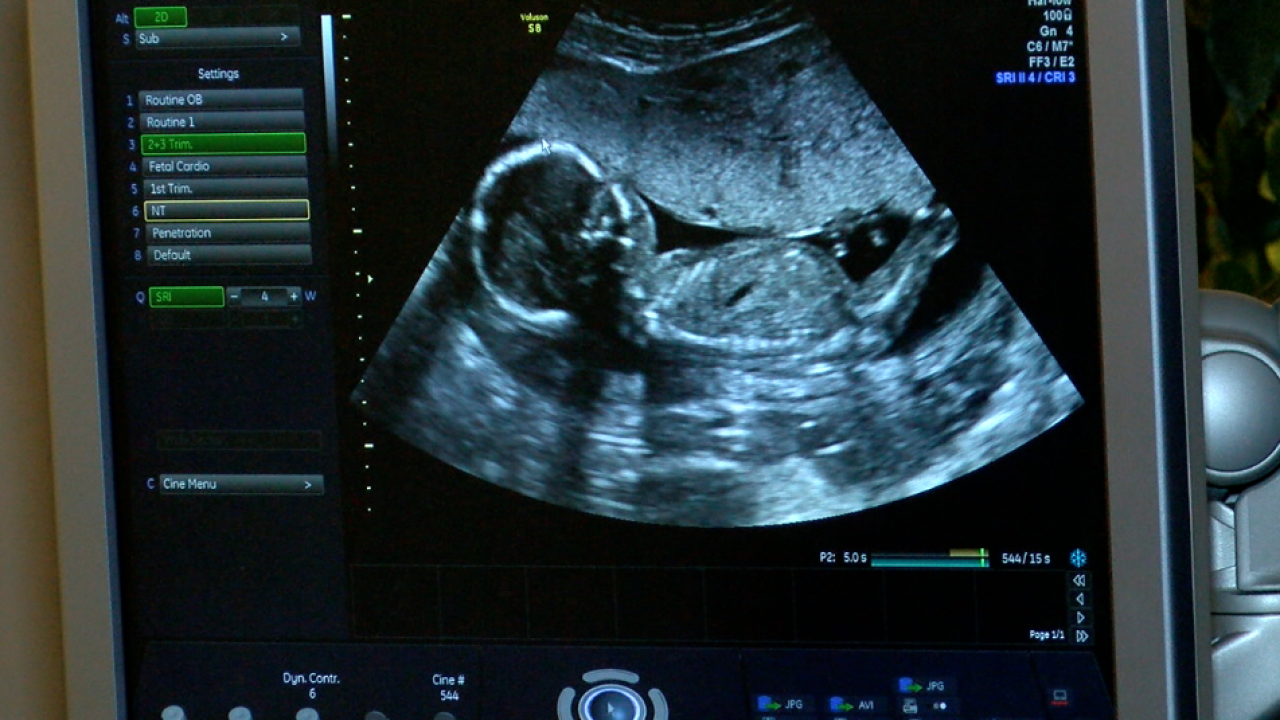

13 Week 3d 4d Ultrasound

13 week 3d 4d ultrasound. 5 color thermal 5 black and white. Early gender boys 15 weeks. Have a gender reveal party. More heartbeat buddies just 40.

At this stage the baby has put on some weight and filled out to make features more visible yet still enough fluid in front of babys face to obtain great images. Surprise mom or make it a planned event. Our gender sonograms start at 13 weeks 5 days. Please call us if you have any questions regarding.

13 weeks ultrasound 3d4d live the gender its a boy. Early gender girls 13 weeks. Refreshments and a sweet treat dvd of your session 20 value. Gender ultrasounds as low as 50 ask me how you can find out gender as early as 8 weeks by blood test or 13 weeks by ultrasound.

For news and special offers. However we do recommend a gestational age of 26 34 weeks for the best facial detail. Early gender boys 14 weeks. Unsubscribe from leanne and dillon.

Baby belly bumps 3d 4d ultrasound studio invites you to come experience the difference where the difference is the experience. Early gender girls 15 weeks. 14 weeks length. Elective ultrasounds 2d3d4dhd can only be performed on pregnant women who are under the care of a physician.

Early gender girls 14 weeks. 14 week gender guarantee we show you gender or we bring you back for free. Early gender boys 13 weeks. This session shows your baby in colored 3d4d.

Subscribe subscribed unsubscribe 121k. The entire ultrasound session will be captured from the ultrasound machine and recorded on a dvd which you will be able to watch with family and friends later. 3d 5d ultrasound images and 4d ultrasound video can be obtained at any stage. 2d ultrasound with a quick look at your baby in 3d4d mom 1 guest 2 people total.